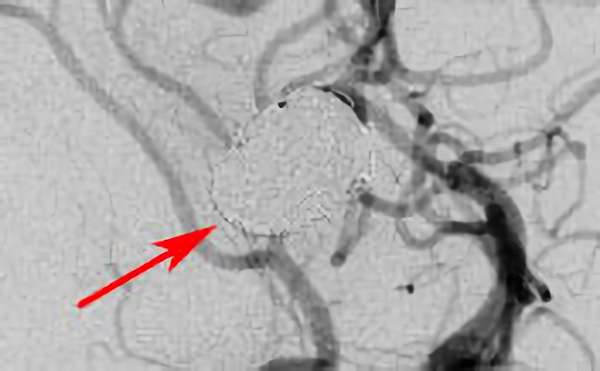

No.1631 手術後